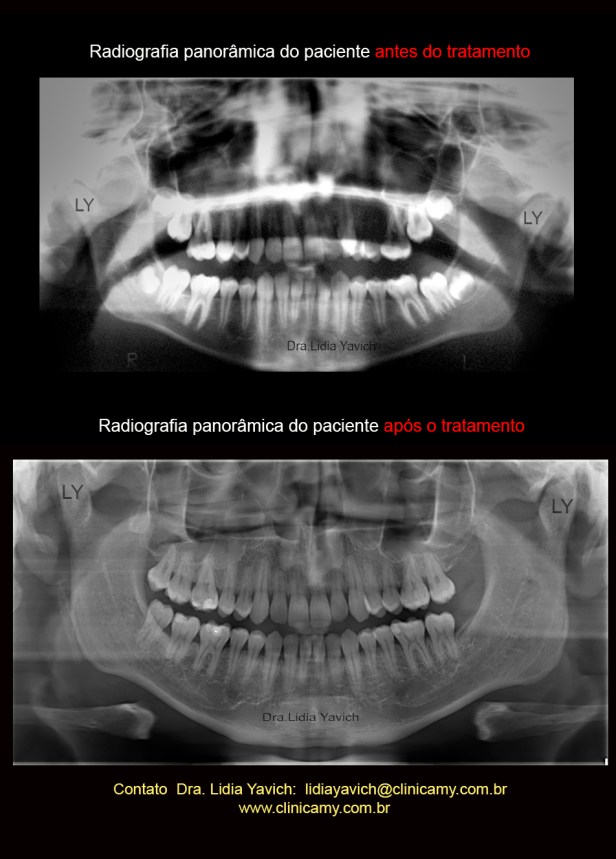

Radiografia panorâmica inicial do paciente no dia da consulta.

Radiografias panorâmicas comparativas: antes do tratamento e após a finalização da ortodontia tridimensional.